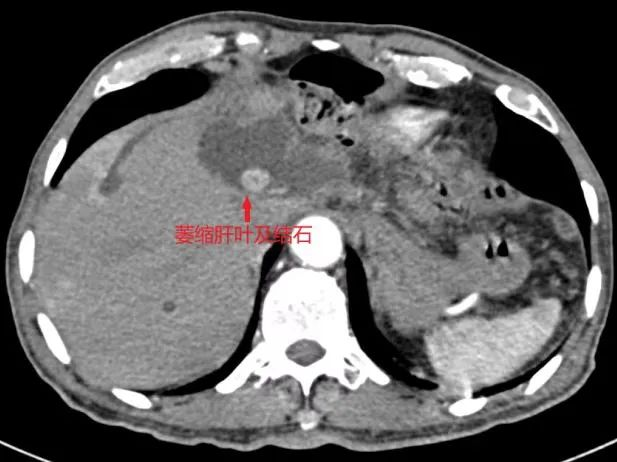

患者入院后,肝胆胰脾外科团队为患者完善了CT、MRCP等检查,发现患者并不是简单的胆囊结石,而是复杂的肝左叶胆管结石伴左肝叶及左尾状叶萎缩。临床上肝内胆管结石反复并发感染,可引起局部肝脏的萎缩、纤维化和功能丧失,甚至癌变。切除病变部分的肝脏,是根治肝内胆管结石的**方法。而肝切除术是非常具有挑战力的手术,手术区域解剖变异多、术中出血不易控制、还有气体栓塞等风险。

针对这例复杂的肝内胆管结石,尤其是作为“肝脏手术禁区”的尾状叶切除术,肝胆胰脾外科主任袁建毛组织科室医护人员经过详细的术前讨论,制定了完善的手术方案。在麻醉科曹晖副主任医师的全程精心护航下,经过三个多小时的手术,成功实施了左半肝切除术+左尾状叶切除术+胆囊切除术+经左肝管胆道胆管探查术。术后病理提示:肝脏导管内**状肿瘤伴低级别上皮内肿瘤,局部腺体中度异型增生,慢性胆囊炎。在23病区全体医护人员的精心治疗和护理下,患者顺利康复出院。